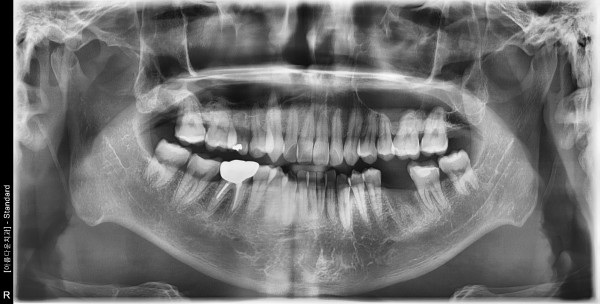

41세 남자 좌측구치부 임플란트식립